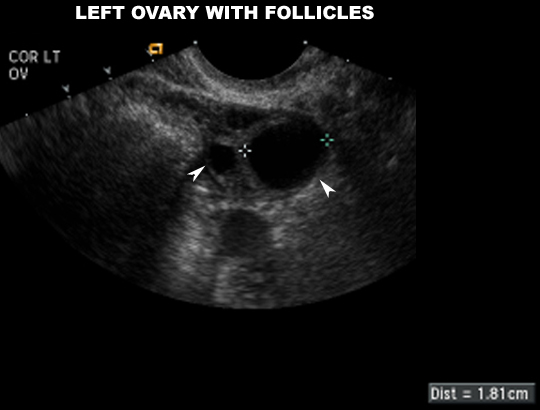

US Pelvis |